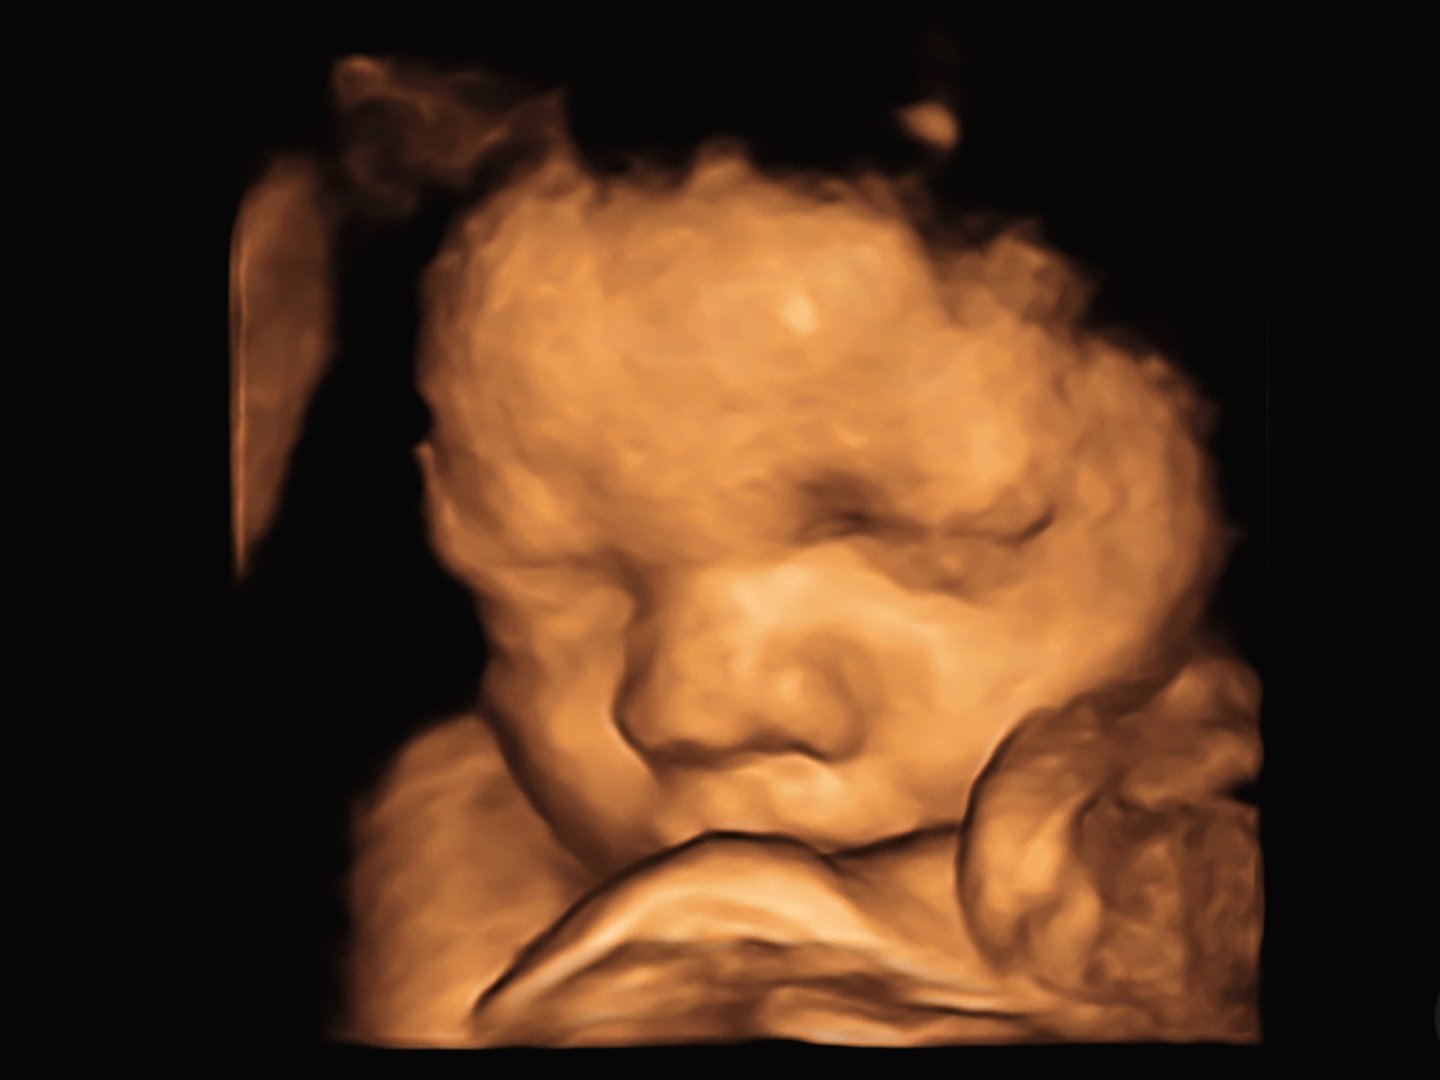

A 3D ultrasound image of a babys face, showing detailed features with eyes closed and a visible nose and mouth.

ULTRASONIDO 4D/5D Y 5D

Ultrasonido general del embarazo con imágenes y videos de la carita de tu bebé a color.